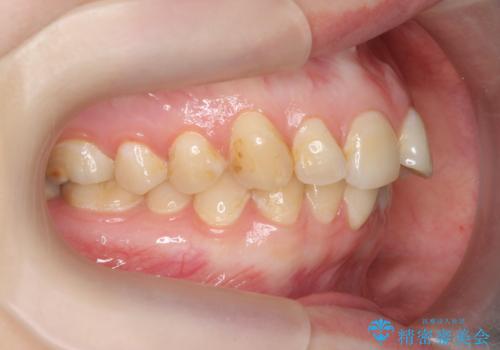

マウスピース矯正で行う出っ歯の治療

- 飛び出したように見える前歯の改善を求めて来院されました。

元々、セラミッククラウンですぐに歯並びを改善したいと希望されていましたが、目立たないマウスピース矯正治療のご提案を行なったところ矯正治療による歯並びの改善を選択されました。

矯正治療を行ったことで出っ歯の改善とともに安定した噛み合わせも手に入れることができました。